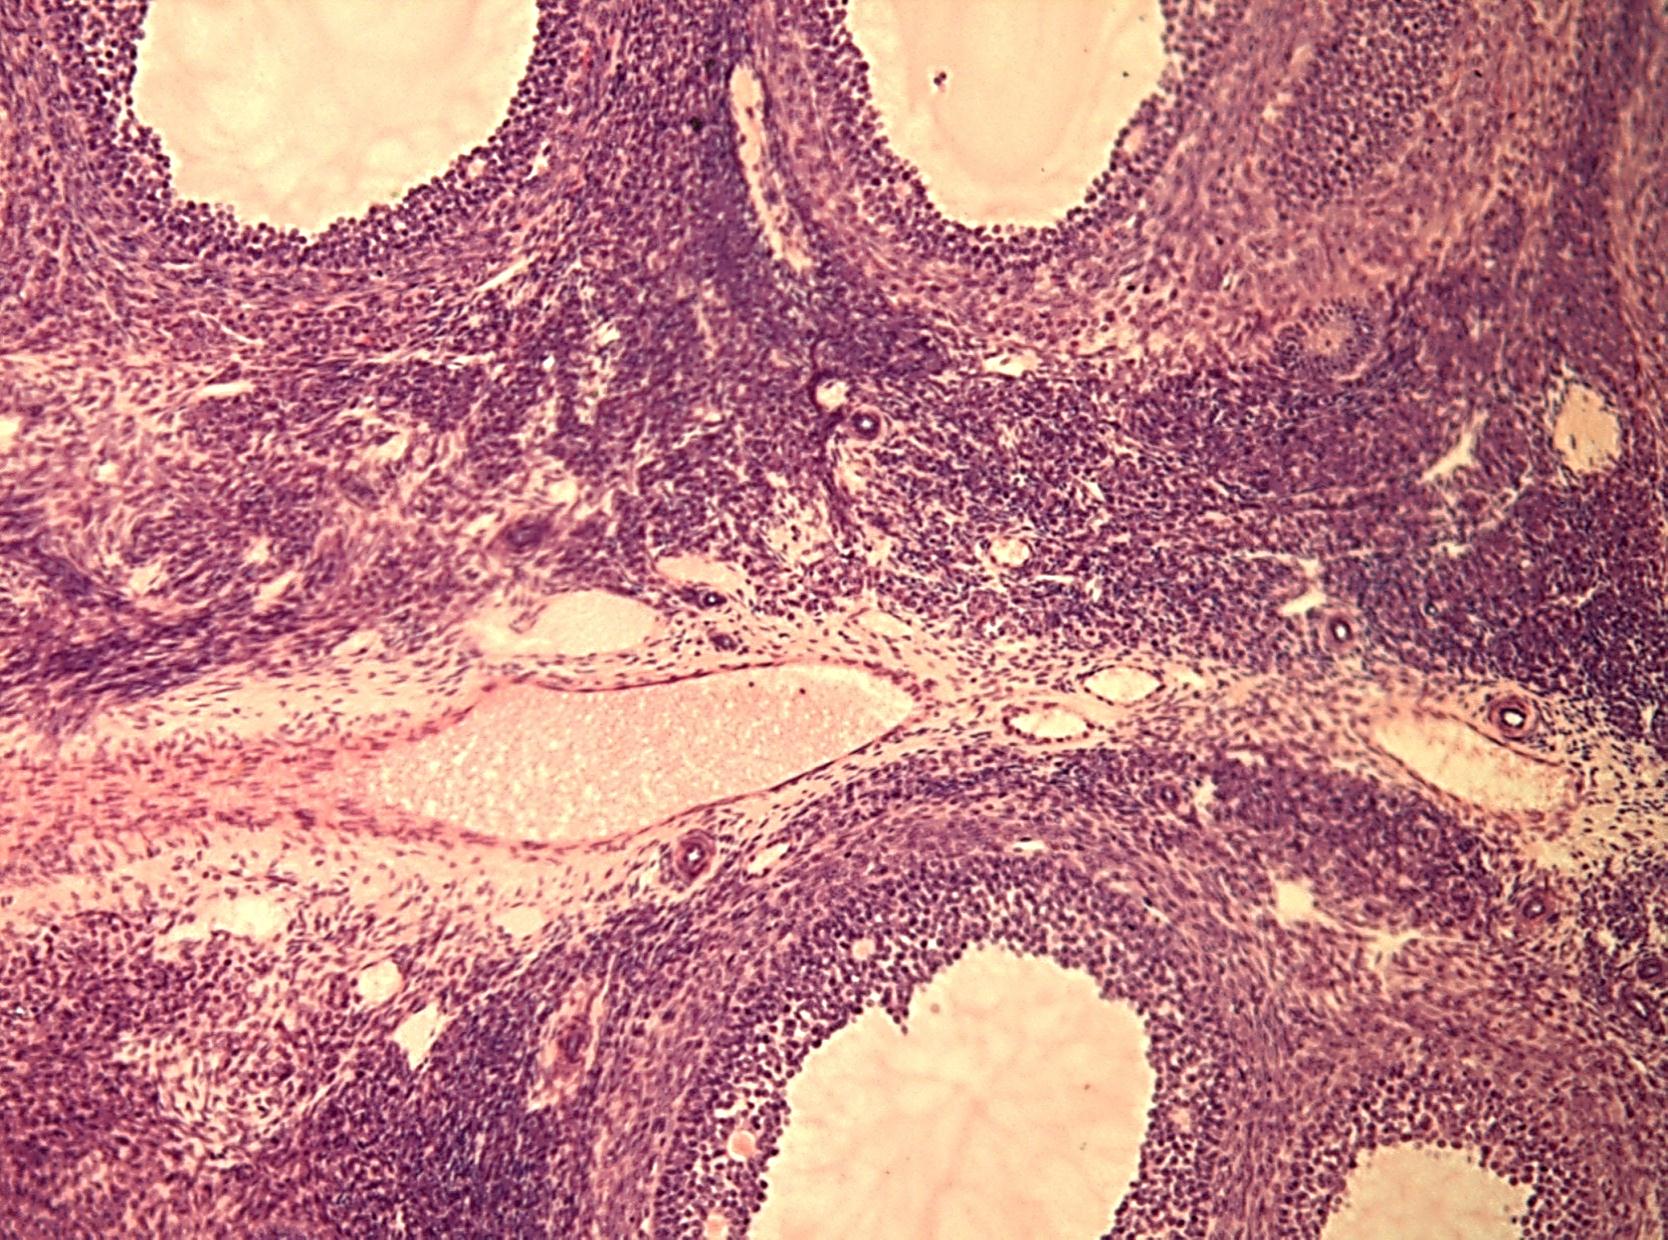

Гистологические изображения фолликулярной кисты яичника